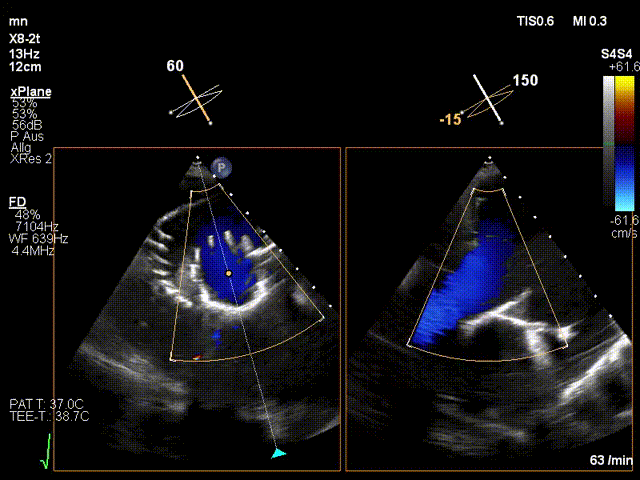

术前三尖瓣大量反流